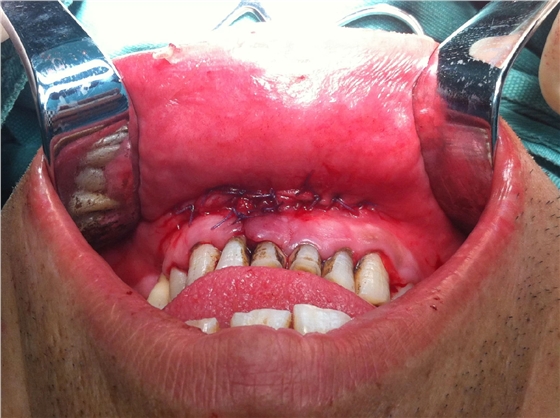

入院后全麻下手術(shù)治療,左側(cè)下頜骨囊腫較大,術(shù)前考慮病理性骨折可能,準(zhǔn)備鈦釘鈦板固定,術(shù)中摘除囊腫后,發(fā)現(xiàn)下頜骨下緣骨量尚可,未給予固定。術(shù)后病理診斷為下頜骨角化囊腫,考慮到患者可能為基底細(xì)胞癌綜合征,術(shù)中切除頸部皮膚痣兩處,術(shù)后病理診斷為:皮膚痣,排除基底細(xì)胞癌綜合征?;颊哂凶髠?cè)第六肋骨分叉肋,綜合以上特征,最終診斷為多發(fā)性頜骨囊腫綜合征。

以上為術(shù)中所拔出患牙及剝離的頜骨囊腫。